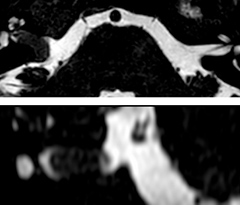

Fast MS protocol with optional sequences

The abbreviated MS protocol for brain is only around 9 minutes, so in case of suspected multiple sclerosis, one or two more advanced sequences may be added, such as PSIR (phase sensitive inversion recovery) or susceptibility-weighted sequences to help us make more confident diagnoses in these inflammatory cases.

In this example, the optional 3D multishot susceptibility weighted sequence with 0.6 mm isotropic voxels is 2 lesions with a central vein sign (arrows) and one lesion with a phase-rim sign (arrowhead). The total scan time, including SmartBrain and axial PD/T2 3mm, is 11:10 min. and is 18:30 min. with the optional 3D PSIR and 3D SWI multishot included.

3D TFE T1

3D FLAIR

DWI image

3D T1w TSE Gd

3D PSIR

3D SWI

“In multiple sclerosis patients, we increasingly include a multishot susceptibility sequence [3] in our routine cases, thanks to the shorter scan times. Our abbreviated MS protocol for brain is around 8 to 9 minutes, so we can ask for one or two additional sequences to visualize the central veins, or to get an additional contrast to better depict posterior fossa lesions. In cases of white matter lesions of unknown significance on FLAIR images, for example when we see high signal hyperintensities in the brain, we can add on more advanced sequences such as PSIR (phase sensitive inversion recovery) or susceptibility-weighted sequences to help us in distinguishing between MS and nonspecific or vascular abnormalities in these inflammatory cases.”